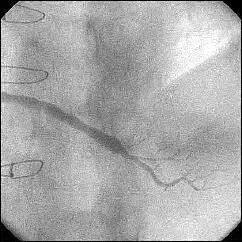

����ALCx take off lesion ��PCI���s���܂����B

�����搶�̌䏕����q�����ċ}篁A�a�i�����搶�j�ɗ���ŗ��Ē����܂����B

CBA(3.5?)+STENT(3.5�~13?)��strategy�ōs������ɂ��Ă��܂������A

�����ő��Z������܂����B

�ƂĂ����p���������̂ł����A�O���ɂق��̐搶��CB(3.5?)���g�p���ꂽ�̂�c��

���Ă��炸�A

�h��������3.5?�o���āI�h�ƌ�������A�h����g�������炠��܂���I�h�Ƃ���

�������Ԃ��Ă��܂����B

��������Stormer(3.5�~15?)��pre������STENT����悤�Ǝv������pre��distal����

�ɑ傫���Ă��܂��A���ǂ����̒ʂ�S670(3.5�~24?)������H�ڂɂȂĂ���

���܂����BCB�������炱��ȂɗȂ����������Ȃ��`�Ƃւ���ł��܂��܂����B

���҂���A�a�A�����Ă��������A�h�o�C�X�����������搶���A�\����܂���B

���x����͑O���ɂ������device�Ƀ`�F�b�N������悤�ɂ��܂��B

�ꉞ�A���ʂ�Y�t���܂��B